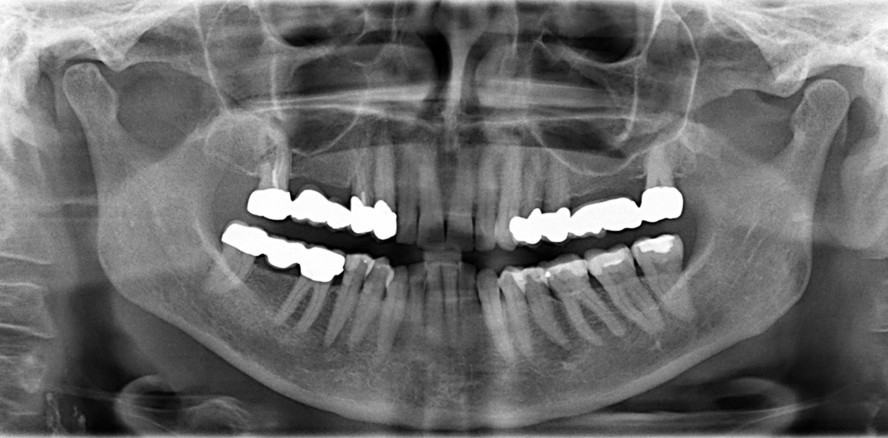

Mikroleakages, die aus einem unzureichenden Verschluss resultieren, stellen eine der ­Haupt­ursachen für endodontische Misserfolge dar. Eine zentrale Komponente zur Erreichung eines dichten Verschlusses ist der Wurzelkanalsealer. Der Autor nimmt uns mit auf eine Zeitreise dieses ­Materials – in Teil 1 vom Start mit MTAs bis hin zu modernen Biokeramiken und ihren ­grund­sätzlichen Eigenschaften.

Die Funktion des Wurzelkanalsealers besteht darin, die Hohlräume zwischen dem Kernfüllmaterial und den Dentinwänden zu füllen und eine dichte Verbindung herzustellen.14 Insbesondere die Penetration des Sealers in die Dentin­tubuli und anatomische Komplexitäten des Kanalsystems ist für eine suffiziente Versiegelung von entscheidender Bedeutung. Zu den Anforderungen zählen eine exzellente Versiegelungsfähigkeit, dimensionale Stabilität, Biokompatibilität, Unlöslichkeit gegenüber Gewebsflüssigkeiten, eine gute Adhäsion an den Kanalwänden sowie eine adäquate Verarbeitungszeit und einfache Handhabung.9, 10

Die Limitierungen von MTAs motivierten die Weiterentwicklung von Materialien, die auf dem Kalziumsilikat-Prinzip basieren, aber verbesserte Eigenschaften aufweisen.17 Die ersten speziell als Wurzelkanalsealer konzipierten Kalzium­­silikat-­zemente wurden im Jahr 2007 vorgestellt. Diese Materialien, zusammenfassend als Biokeramiken bezeichnet, werden nach ihrer Interaktion mit dem Gewebe als bioinert, biokompatibel oder bioaktiv klassifiziert.9 Moderne biokeramische Formulierungen basieren auf Kalziumsilikaten, Kalziumphosphat und Kalziumhydroxid, wobei als Röntgenkontrastmittel häufig Zirkoniumoxid anstelle von Bismutoxid verwendet wird, um Verfärbungen zu vermeiden. Ihr wesent­licher Vorteil ist die Bioaktivität: Bei Kontakt mit Gewebs­flüssig­keiten initiieren sie die Bildung von Hydroxylapatit, was zu einer chemischen Anbindung an die Dentinstruktur führt.17 Zudem schaffen sie durch die Freisetzung von Kalziumionen und Hydroxidionen ein hochalkalisches Milieu, das den periapikalen Heilungsprozess begünstigt.9 Diese Weiterentwicklungen führten zur Verfügbarkeit verschiedener Konsistenzen, darunter fließfähige Sealer und formbare Putty-Materialien für spezielle Repa­ratur­indika­tionen. Insbesondere die hydrau­lischen Kalziumsilikat-Sealer haben zudem vereinfachte Obturationstechniken, z. B. die Single-Cone-Methode, wieder in den Fokus der klinischen Anwendung gerückt.10